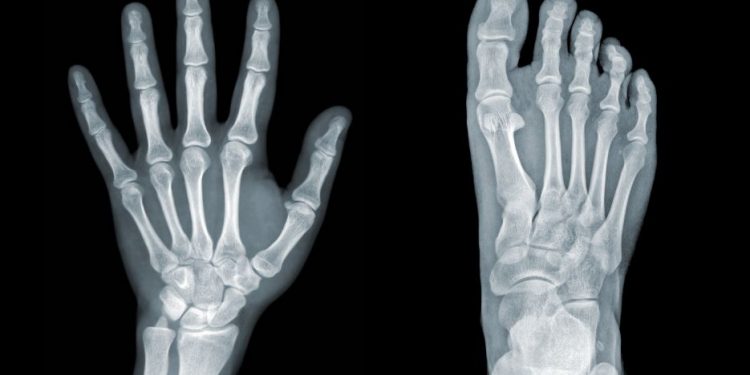

The diagnosis of hypertrophic osteoarthropathy requires clinical examination and a bone scan. A technetium bone scan can show the presence of thickening of the bones. This thickening can be seen along the cortex and can be present in non-muscular locations. The thickening can cause tenderness or a burning sensation in the affected area. X-rays can also be used to diagnose the disease. X-rays of the wrist, femur, and tibia may show the periosteal elevation associated with hypertrophic osteoarthropathy. In most cases, the treatment is simply symptom control. Treatments can include anti-inflammatory medication, corticosteroids, bisphosphonates, and octreotide.

Patients with HPOA may also experience symptoms such as swelling and excruciating deep joint pain. These symptoms may be present in both children and adults. In children, the disease may be present at an earlier age than adults. The symptoms may also include a clubbing deformity of the fingers. The clubbing deformity can be caused by the growth of subungual connective tissue. The growth can cause the nails to grow out or develop drumstick appearances on the nail beds. The deformity may also be caused by a lack of oxygen in the blood.

The symptoms of HPOA can vary, but the most common symptoms are pain, swelling, and excruciating deep joint pain. People with HPOA may also have a burning sensation in their hands and feet, as well as painful joint effusions. This is unlike inflammatory arthritis, in which the affected area will appear red and swollen. If you notice pain in your hands and feet, see a doctor immediately. You can also take NSAIDs and other medications to help control the pain.